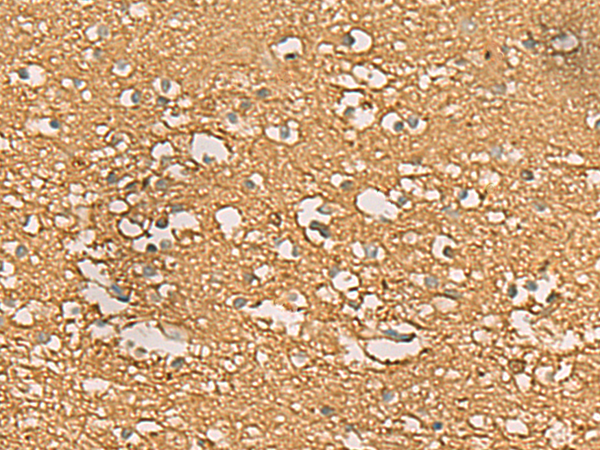

分类: 科研抗体货号: P02876别名: HC9; PSC9; HsT17706应用: WB,IHC反应种属: Human, Mouse, Rat